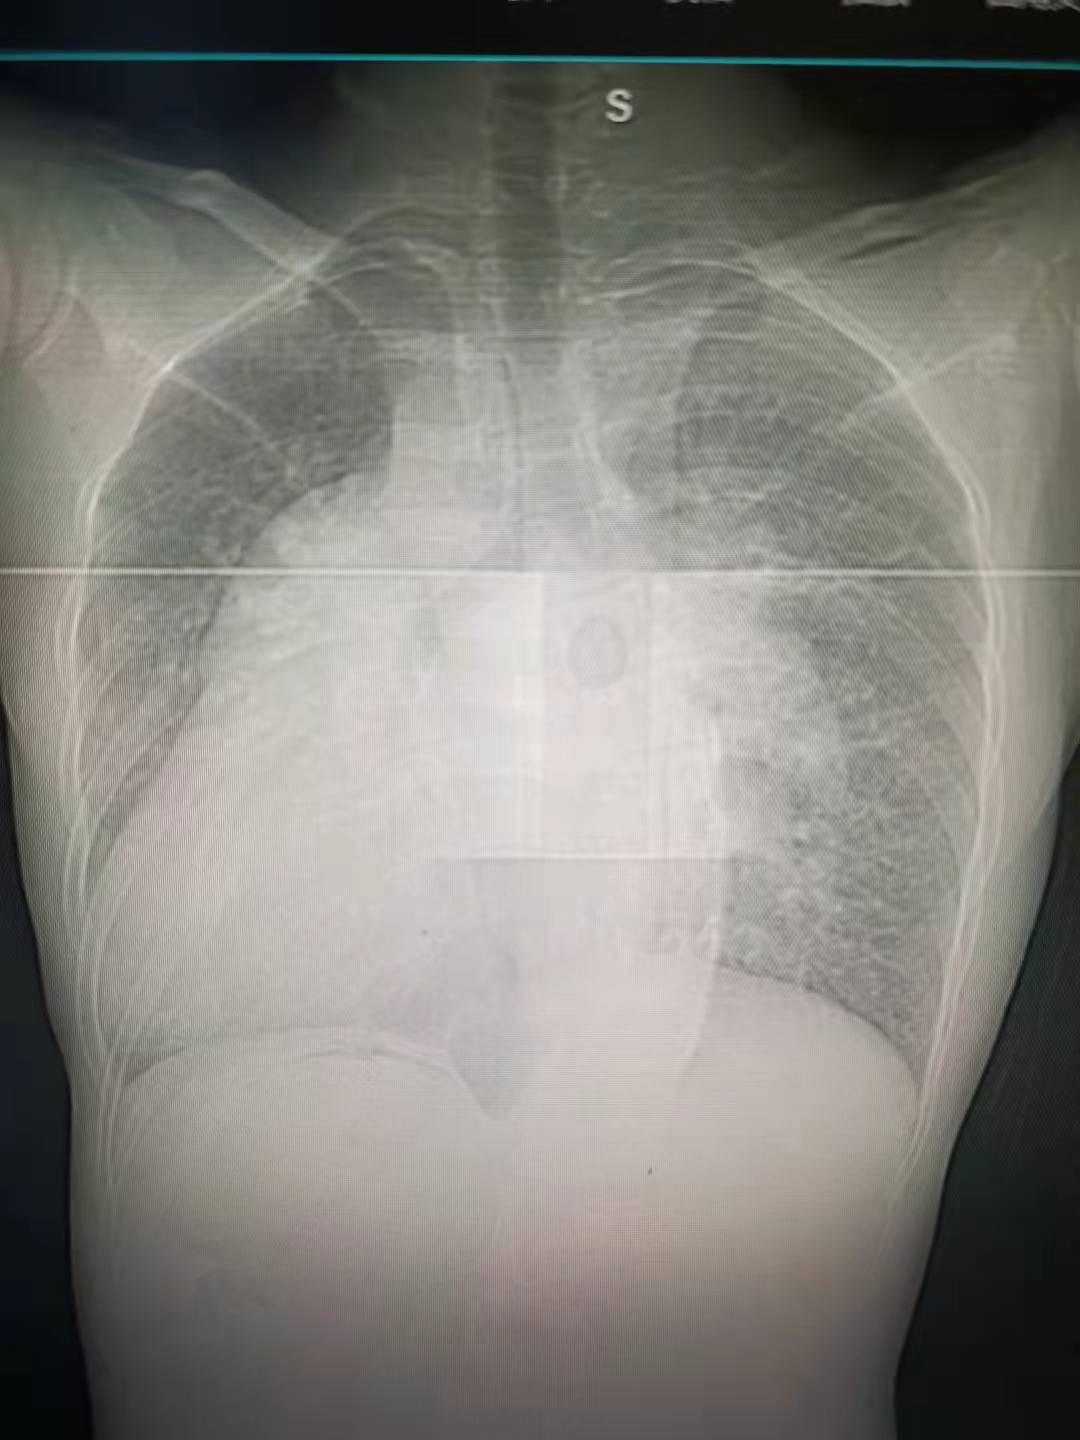

“镜像人”,其心脏、肝脏、脾脏、胆等器官的位置与正常人相反,如同正常脏器的“镜中像”。

近日,上海市第一人民医院南部心脏及大血管外科收治了一位先天性心脏结构异常(镜像右位心)患者,并成功为其实施了室间隔缺损修补术。

接受手术的男性患者今年27岁,因先天性脊柱侧弯来市一医院南部脊柱外科就诊,完善术前准备时发现患者为“镜像右位心”,合并有膜周部大室缺(左向右分流)、重度肺动脉高压(收缩压108mmHg)。腹部超声提示内脏位置倒转,是一位典型的“镜像人”,同时合并有先天性脊柱侧弯,情况十分罕见。

术中发现患者全心增大,肺动脉增粗、压力增高,探查室缺发现膜周部巨大室缺,大小约3*3.5厘米,手术团队随即应用涤纶补片成功修补室缺。

【 手术|男子就医意外发现自己是罕见“镜像人”,五脏六腑全长反,医生这波“反向操作”厉害了】手术十分顺利,患者术后被送至监护室观察康复。术后第一天,患者即顺利拔除气管插管,第三天转入普通病房继续治疗,复查心超提示镜像右位心、室缺修补术后,未见残余漏,肺动脉压降至50mmHg,并于近日出院。

据悉,镜像右位心又称“真正右位心”,其主要特点是右位心伴内脏反位,即心脏和大血管的位置关系以及胸腹腔脏器的位置完全倒转。该病常单独作为一种心脏畸形存在,但无症状出现,亦可无血液动力学改变,可不治疗。部分病例可合并其他心血管畸形,如大动脉转位、右室双出口、房间隔缺损、室间隔缺损等,并发率常低于10%,需要及时手术治疗。